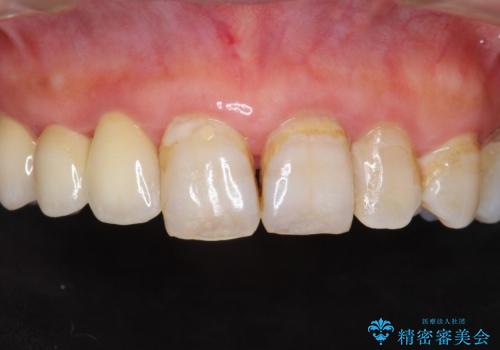

ブリッジとクラウンの自然な仕上がりと咬み心地に喜んで下さいました。

精密な根管治療により、下の前歯の歯ぐきにできていた瘻孔もなくなりました。

短期間(2ヶ月)でしっかりとした治療が受けられたとご満足頂けました。

右上④3②ブリッジ:オールセラミッククラウン スタンダード

右下1クラウン:オールセラミッククラウン エコノミー